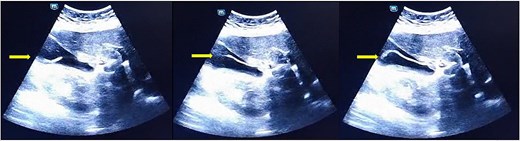

A 41-year-old woman with no significant medical history presented to the emergency department with abdominal pain marked in the right hypochondrium and epigastrium. This was associated with four episodes of postprandial vomiting of 3-day duration. Physical examination revealed tenderness in the epigastric and right hypochondrium regions. She was admitted and underwent an abdominal ultrasound, which revealed acute cholecystitis with vesicular sludge as a notable sign. Blood tests showed mild hypokalemia (3.1 mmol/L), C-reactive protein at 7.23 mg/L, and a white blood cell count of 4730 with an eosinophil count of 1.3% of white blood cells. We suspected hepatic colic. Since no biological disorder was identified, we had a second radiologist perform an ultrasound, which allowed us to visualize a floating and zigzagging central anechoic tube that lacked shadowing in the gallbladder with no signs of cholecystitis (Fig. 1 and Video SS1). This finding is consistent with the presence of worms swimming inside the gallbladder. We completed our history with the patient, who admitted that she did not take deworming medication regularly. She also admitted to having episodes of nocturnal cough 2 weeks earlier, which had improved without treatment. This finding was suggestive of Loffler’s syndrome. We concluded that the patient had vesicular Ascaris lumbricoides. The stool test was not available in emergencies or at weekends. The patient was treated with 400 mg of albendazole and amoxicillin combined with clavulanic acid and was monitored for 3 days in the hospital. The outcome was favorable, and the patient was followed up over a month with no recurrence and ultrasound was normal. She was advised on preventive and hygienic measures.

Floating and zigzagging central anechoic tube which lack of shadowing into the gallbladder.